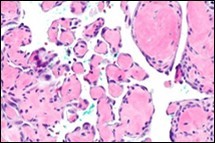

On microscopy, superficial squamous epithelial surface is intact. Sub-epithelial connective tissue stroma exhibits slit-like, vascular spaces. Upon extended magnification, multiple, intravascular papillary projections encompassed within a hyalinised stroma are discerned. Centroidal calcification appears in combination with intravascular, papillary endothelial cell proliferation, lined with singular layer of endothelial cells devoid of cytological atypia6, 7.

Characteristically, the vascular neoplasm denominates numerous papillae within blood vessels. Papillae are coated with singular or dual layer of flattened endothelial cells with an encompassing hyalinised, fibrous tissue core. Vascular lumen is distended with thrombosis. Foci of haemorrhage with fibrinous and purulent exudate are discerned. Tumour perimeter depicts inflammatory granulation tissue. Cholesterol clefts and focal reactive bone formation may concur. Extraneous squamous epithelium may be discontinuous and ulcerated. The neoplasm is devoid of features of malignancy4, 6.

Numerous micro-calcifications can be observed within the lesion which may engender vascular occlusion and tissue necrosis6. Figure 1, Figure 2, Figure 3, Figure 4, Figure 5, Figure 6, Figure 7, Figure 8.

Figure 1 Papillary endothelial hyperplasia elucidating papillary articulations layered with a single layer of endothelial cells and a commingling of fibrinous, thrombotic exudate 10.